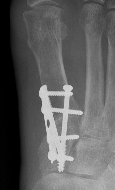

Lapidus Procedure / TMT arthrodesis + DTSP

Indications

- moderate to severe HV

- TMTJ hypermobility

- metatarsus primus varus

Technique

Triplanar correction - coronal / sagittal / rotational

Results

Do et al Orthop Clin North Am 2022

- systematic review of 1800 Lapidus

- complication rate 17%

- hardware pain 3%

- nonunion 3%

- delayed union 2%

- wound complication 1%

Fixation

- screws / plate / screws + plate